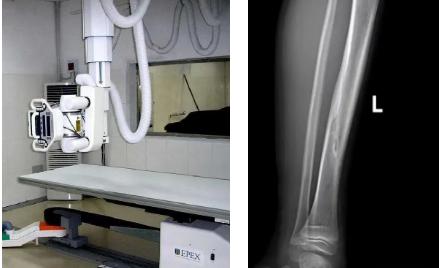

一般骨科創(chuàng)傷的病人,只要到影像科拍一張X光片,很快就會(huì)明確診斷有沒有骨折。然而有一些特殊類型骨折的病人,由于拍片影像重疊的緣故,或者骨折未發(fā)生明顯移位,病變可能顯示不出來,等過了一段時(shí)間后,骨折部位才能夠顯示清楚。這種類型的骨折,叫做隱匿性骨折。若在臨床上診斷及時(shí)且明確,及時(shí)固定患者的骨折部位,進(jìn)行適當(dāng)治療并減少運(yùn)動(dòng),對(duì)患者的恢復(fù)有重要意義。

1.定期復(fù)查。一般于骨折后2-4周,骨折進(jìn)入骨痂期,骨折斷端有新生骨形成,呈明顯高密度,無論是X線或是CT,都能比較清晰觀察到,通過前后圖像對(duì)比,較容易診斷隱匿性骨折。